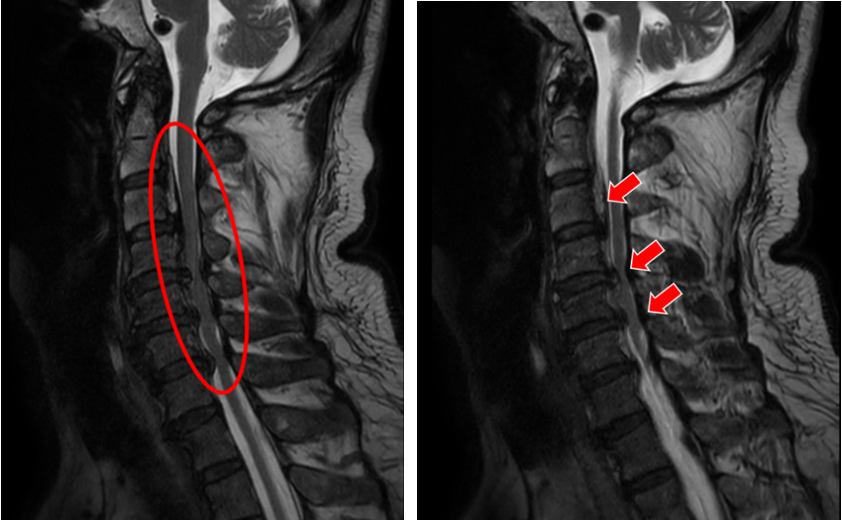

就在张老爷子术后没几天,他的儿子张先生也住院了,父子俩被特意安排住在同一间病房。84岁老父亲第二次手术的成功给了张先生极大的鼓舞与信心,多年来对手术的恐惧感也减轻了不少。就在父亲术后第八天,张先生也接受了颈椎后路椎管扩大成形术。

(颈椎CT显示张先生C2-6椎体后纵韧带广泛骨化,椎管狭窄明显)

(颈椎MRI提示C2-6椎管狭窄,脊髓受压严重)

术后第一天,他就感觉自己四肢麻木明显缓解,效果可谓立竿见影,这让他喜出望外,坦言早该积极接受治疗。俗话说久病成良医,张先生这些年来对颈椎病的研究可没少下功夫,他知道这种病拖得越久,越不利于康复。他告诉姜主任,等他出院后,一定现身说法,告诉其他病友:得了颈椎病该手术的,一定不要犹豫不决,免得耽误了治疗的最佳时机。